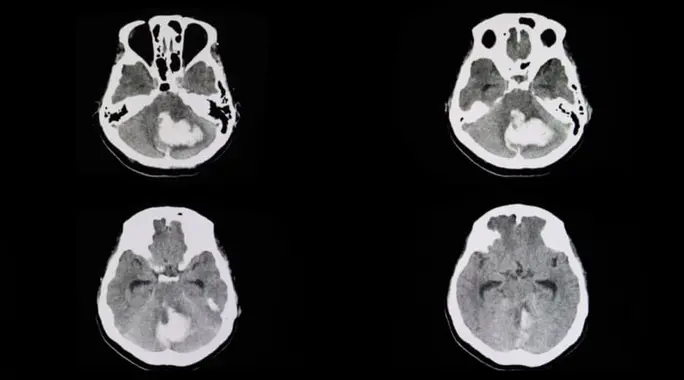

يتطلب تشخيص جلطة المخيخ دقة وعناية، خاصة وأن المخيخ محمي بعظام الجمجمة، مما قد يعيق رؤيته بوضوح في بعض الفحوصات:

- التصوير المقطعي المحوسب (CT): غالبًا ما لا يكشف التصوير المقطعي المحوسب عن جلطات المخيخ بفعالية بسبب موقع المخيخ المحمي.

- التصوير بالرنين المغناطيسي (MRI): يُعد التصوير بالرنين المغناطيسي الأداة التشخيصية الأكثر فعالية للكشف عن جلطات المخيخ، ويفضل اللجوء إليه في الحالات الطارئة للحصول على صورة واضحة ومفصلة.